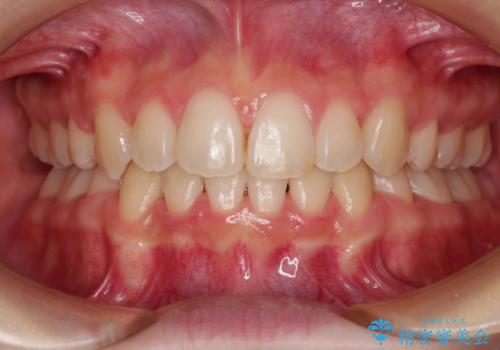

インビザラインによる矯正治療(非抜歯) 前歯の捻れとガタつきの改善